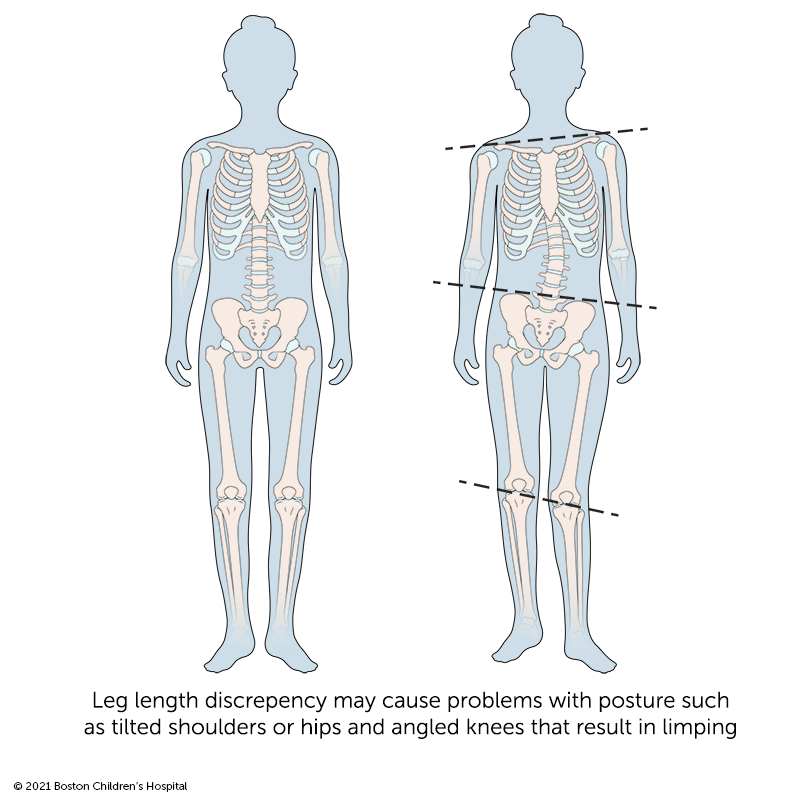

Compared to differing arm lengths, leg-length discrepancies are more likely to affect a child’s daily activities. Legs of two different lengths require children to change their normal posture and walking patterns. Depending on the degree of difference, leg-length disparities can lead to a variety of problems, such as functional scoliosis, and hip, knee, and ankle problems.

If your child has a leg-length discrepancy, the doctor may watch your child walk to look for signs that they are compensating for their different leg lengths. Their doctor may also ask your child to stand with a block under their shorter leg to measure the amount of correction needed to bring their hips and the rest of their body into alignment.